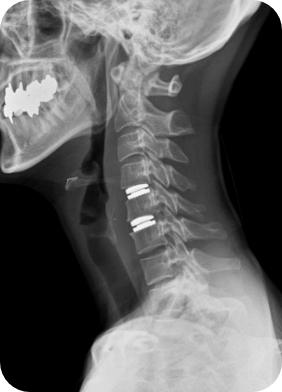

경추 인공디스크치환술

경추 인공디스크란 목디스크 환자에게서 수술후에도 분절간 운동 범위를 유지 하기 위해 시행하며, 손상된 디스크를 제거 후 이식하는 뼈 대신 인공디스크를 삽입하는 치료법입니다.

수술 후 정상 기능을 최대한 보존하며 목도 자유롭게 움직일 수 있는 장점이 있습니다.

피부를 최소절개한 후 신경을 누르고 있는 디스크를 제거한 뒤 인공디스크를 삽입하게 됩니다.

척추유합술과 수술법은 유사하나 인체 디스크와 유사한 인공디스크를 삽입하는 방법의 치료입니다.